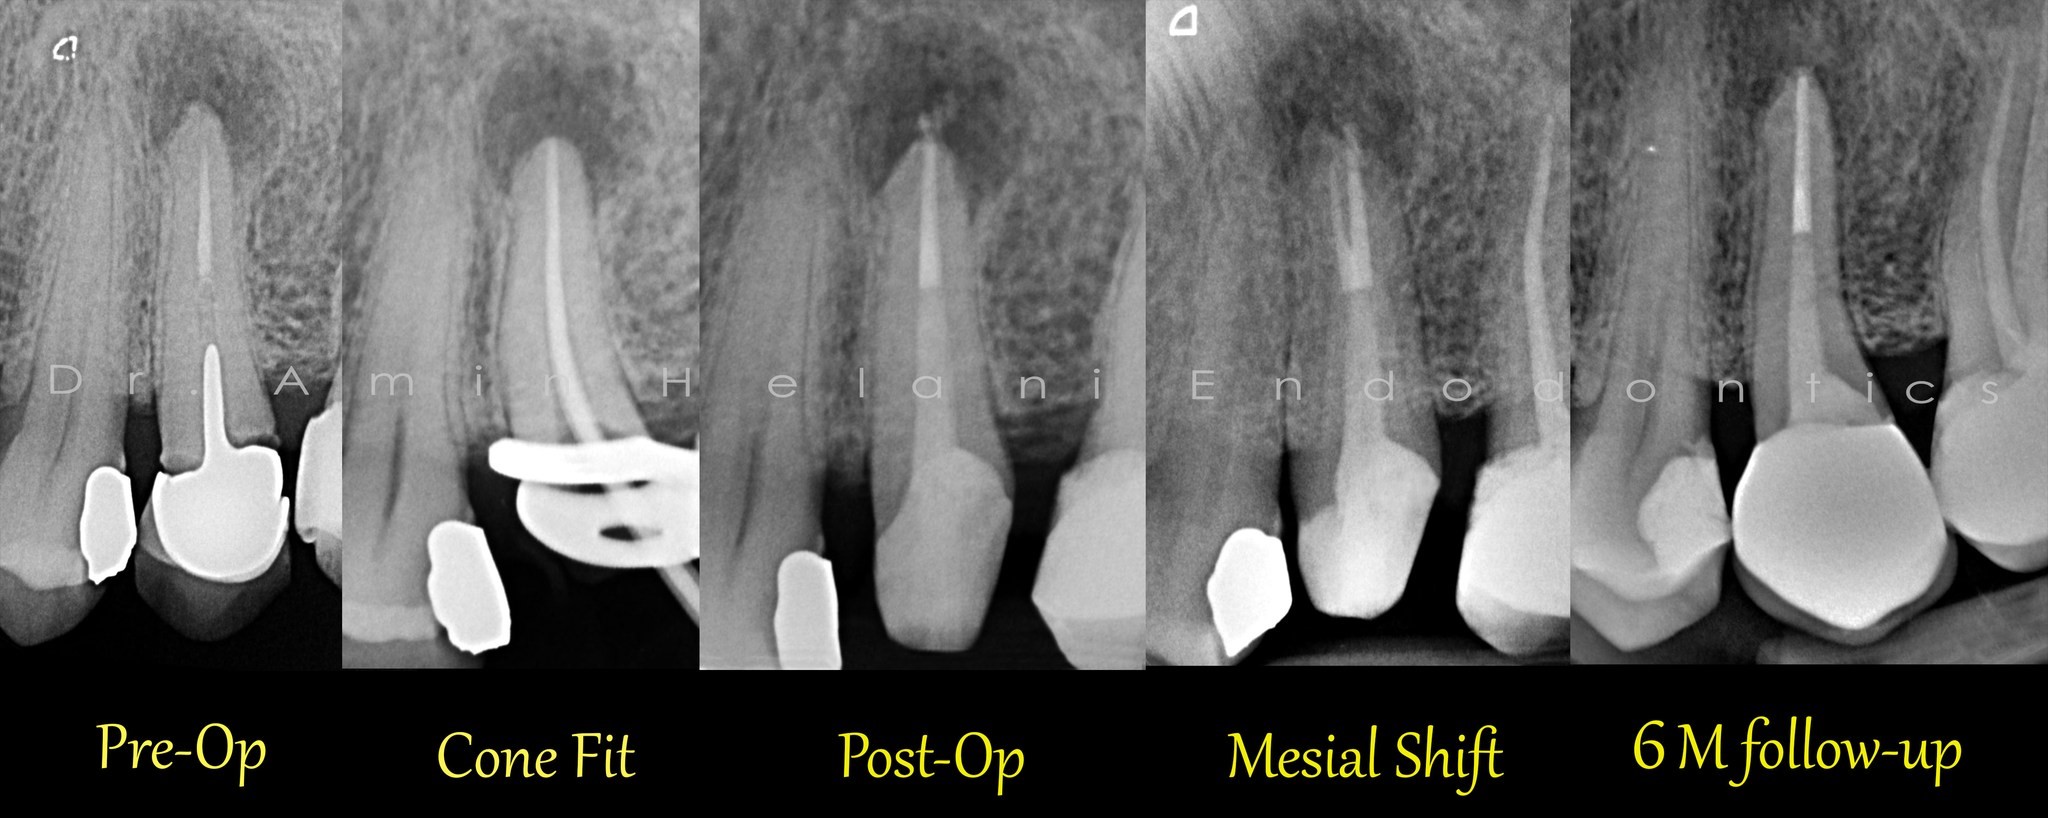

Verkalkte obliterierte Kanäle